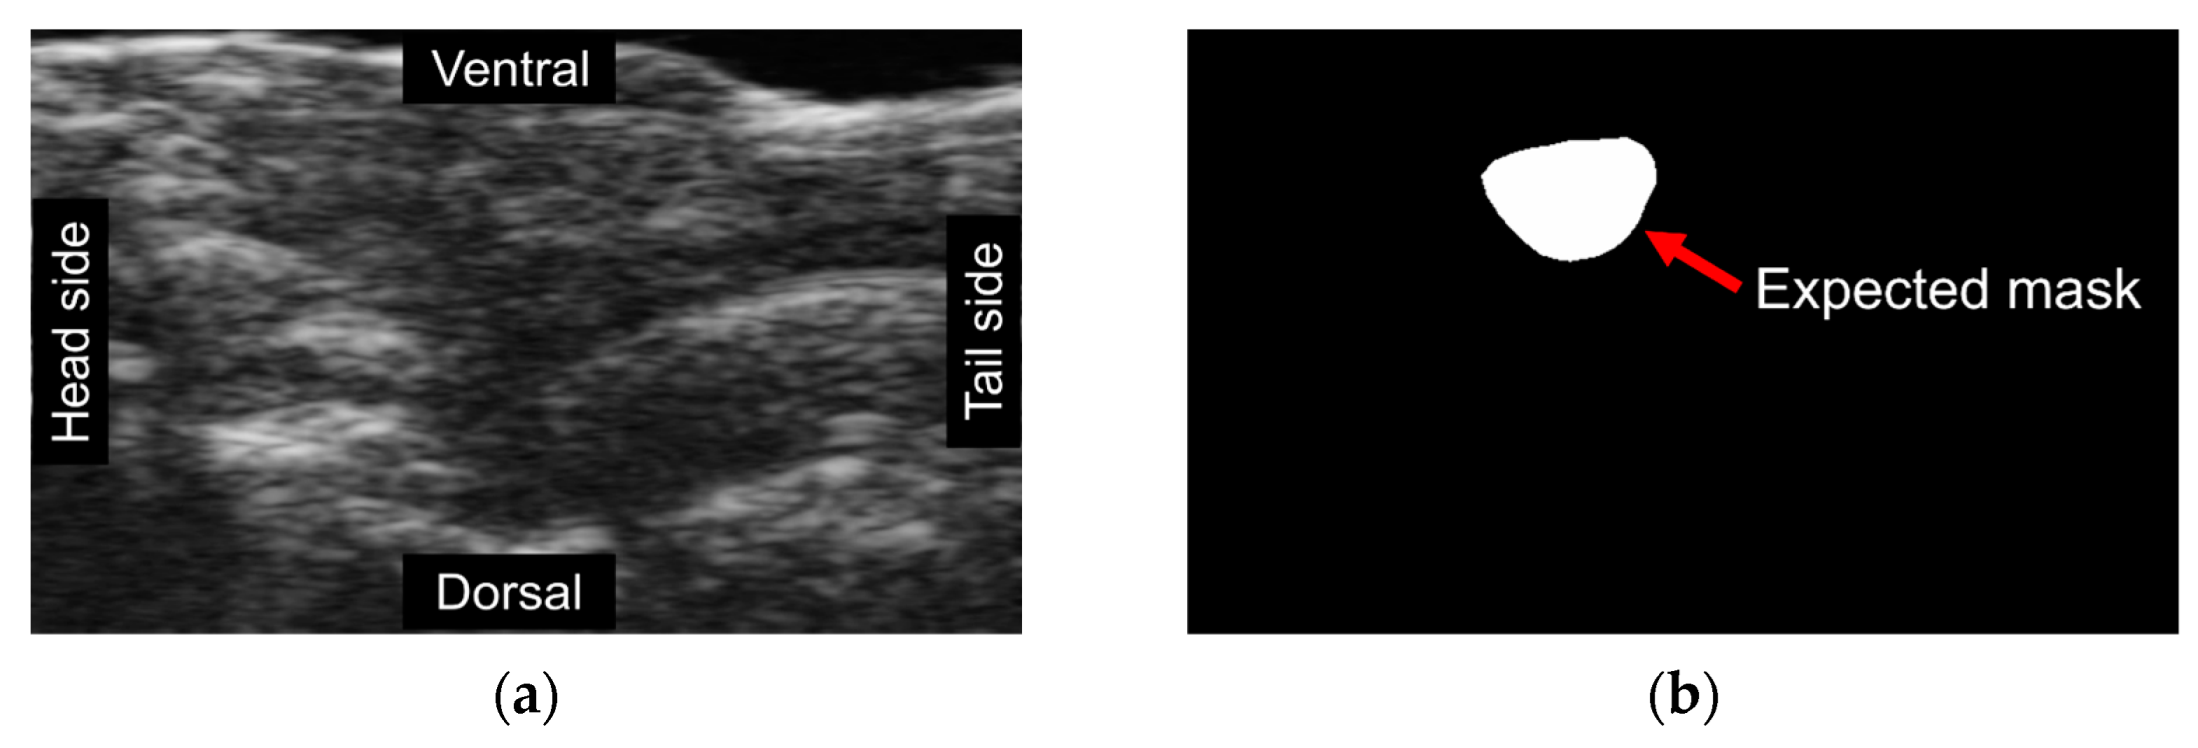

The present study aimed to develop a method for automatically calculating ejection fraction (EF) in fish populations using image processing techniques (Figure 6). The method’s performance was evaluated by comparing its results with manual assessments of the EF by three experienced biologists. The methodology involved detecting the ventricle area and subsequently measuring its size and the left axis length (LAX) from selected frames. A set of 51 videos containing three groups of fish was utilized for the evaluation, with manually labeled frames being chosen for the analysis. The obtained results indicated that the error rate ranged from 0.11% to 37.05% (Figure 7). Results from our automatic EF evaluation are consistent with manual measurements by each of the three biologists. A significant reduction of cardiac function in the AIC model can be detected (Figure 8). Notably, the average error was 9.83%, indicating the high accuracy of the automatic EF evaluation. The study reveals that the proposed method is promising to enhance the efficiency and accuracy of EF calculation in zebrafish.

Figure 6.

Comparison of automatic and manual volumes measurements. The solid lines in the figure corresponded to the ventricle contour and the LAX and detected by the proposed method. The cropped images, labeled manually with dotted lines, correspond to the manual label for each frame. The figures in the same row were selected from the same fish group, and the measurements are in pixels.